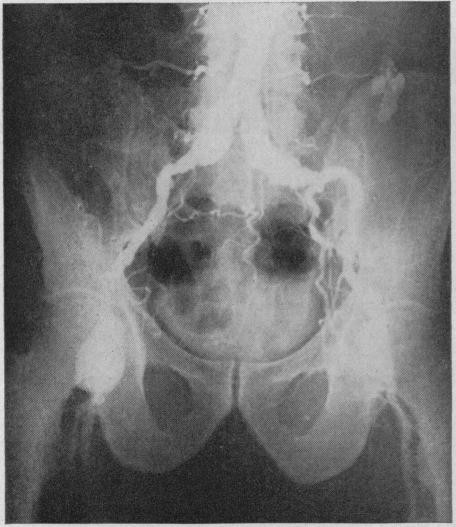

Aortography is valuable in the demonstration of vascular blocks, in determining the exact location of the disease and as a guide to surgeons if operation is done. Since complications may develop, indications for the procedure should be carefully considered. One death and 15 nonfatal complications occurred in 594 cases in which the authors made angiographic examinations.A technique is described which takes a minimum of time.

主动脉造影对于显示血管阻塞、确定疾病的确切位置以及在进行手术时为外科医生提供指导很有价值。由于可能会出现并发症,因此应仔细考虑该检查方法的适应证。在作者进行血管造影检查的594例病例中,发生了1例死亡和15例非致命性并发症。本文描述了一种耗时最短的技术。